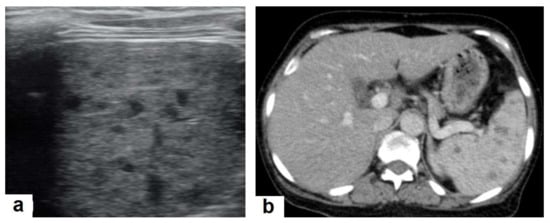

• Miliary TB (Figure 6 and Figure 7) appears as innumerable small (1–3 mm) granulomas with random distribution in the lungs and other organs with a predominance to the lung bases due to the gravity-dependent high blood flow. It occurs due to the hematogenous dissemination of mycobacterium tuberculosis bacilli, especially in immunocompromised patients and children [1,13]. Miliary TB is a significant differential diagnosis of pulmonary metastasis from thyroid cancer or others, even in children [19].

Figure 7. Miliary TB in an adult female with fatigue and loss of appetite. (a) Splenic ultrasonography shows multiple small hypoechoic granulomas with random distribution in the spleen. (b) Axial abdominal CT shows small non-enhancing granulomas with random distribution in the spleen clearly seen during the portal venous phase with multiple enlarged lymph nodes around the portal vein.